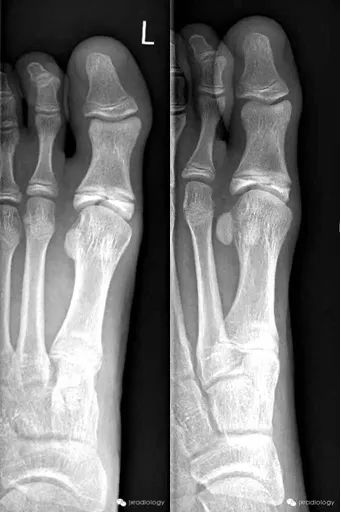

骨骺裂必须和骨折鉴别。一般骨折损伤2-3周后复查平片可见愈合的迹象。识别这个现象是重要的,以避免过度治疗和不必要的手术干预。

骨骺裂必须与骨折相鉴别。通常,如果在受伤后 2-3 周重复 X 线检查,骨折就会显示出愈合迹象。识别该实体对于避免过度治疗和不必要的手术干预非常重要。骨骺裂意译为骨骺裂,结合临床病史及复查才能和骨折区分。

骨骺裂

黄箭骨折;蓝箭是骨骺裂。留下轻微的外侧髁骨折。位移小于 2 毫米,可能很稳定。对一个不同的案例。倾斜的视图给人留下了断裂的良好印象。蓝色箭头表示桡骨骺裂(正常变异型)